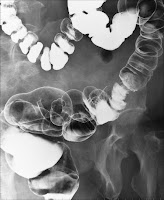

rauma Radiologi adalah suatu jenis pemeriksaan radiologi yang mana ditujukan bagi seorang radiografer untuk dapat membuat gambaran sebaik dan sejelas mungkin dari pasien – pasien trauma yang kebanyakan tidak kooperatif dalam menjalankan pemeriksaan rontgen. Trauma Radiologi yang biasa dijumpai pada bagian Instalasi Gawat Darurat sebuah rumah sakit dapat menjadi sebuah pilihan lingkungan pekerjaan yang menarik dan menantang bagi seorang radiografer. Namun ,tidak dapat dipungkiri juga kasus – kasus trauma radiologi pun dapat menjadi sebuah pekerjaan radiografi yang menakutkan atau bahkan membuat pusing kepala. Perbedaan teknik pemeriksaan yang harus dilakukan terhadap pasien yang bukan kasus trauma dengan pasien yang mengalami kasus trauma amat bergantung pada persiapan seorang radiografer dalam menangani situasi tersebut. Tanggung jawab dalam penatalaksanaan pemeriksaan kasus trauma radiologi ini menjadi sesuatu yang tak dapat disepelekan oleh seorang radiografer.

Radiografer pasien trauma sangat dituntut terampil dan cekatan dalam menangani pasien dengan tetap menghasilkan gambaran radiografi dengan kualitas terbaik. Gambaran harus dapat memberikan informasi sebanyak – banyaknya mengenai kondisi pasien guna penanganan medis lebih lanjut. Di samping itu seorang radiografer pun tidak boleh acuh atau bersikap cuek bila menangani kasus kasus trauma. Tetap bertanggung jawab dalam memperhatikan pasien tersebut dan selalu memberi penanganan terbaik layaknya menangani pasien bukan trauma.